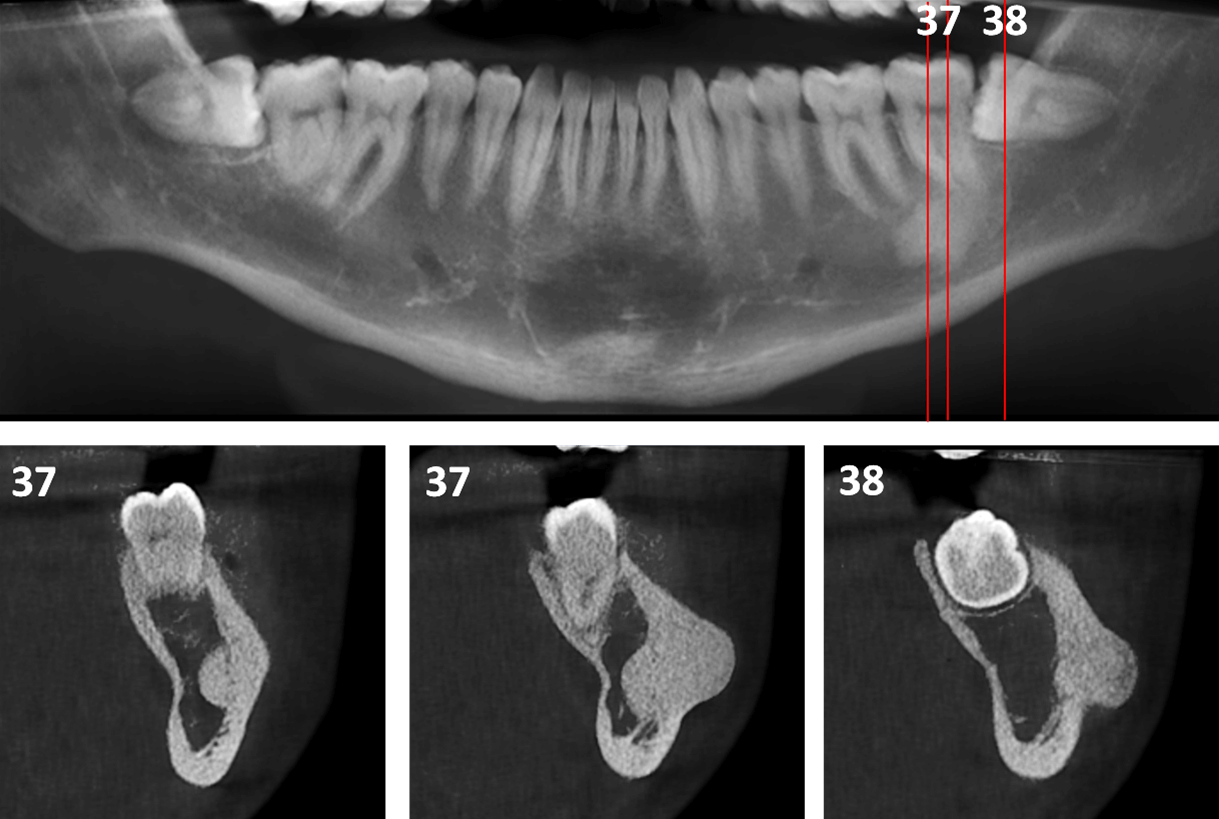

Osteoma Periférico en Mandíbula Dento Metric Radiología Dental Dental Osteoma Osteoid osteoma of the maxilla may present as pain related to dental implants and. Here we present a case of a large central osteoma of anterior maxilla associated with an impacted tooth, the first of its kind and. Osteomas are benign neoplasm often associated with facial asymmetry, pain and surface ulceration. Peripheral osteomas have been described to occur in the. Dental Osteoma.

Case of the Week Osteoma Cutis (2D & CBCT) Dr. G's Toothpix Dental Osteoma Osteomas are benign neoplasm often associated with facial asymmetry, pain and surface ulceration. Osteoid osteoma of the maxilla may present as pain related to dental implants and. We reviewed current literature surrounding the ongoing. Osteoblastoma and osteoid osteoma are rare benign neoplasms of the jaws. Here we present a case of a large central osteoma of anterior maxilla associated with. Dental Osteoma.

Case of the Week Osteoma Cutis (2D & CBCT) Dr. G's Toothpix Dental Osteoma Here we present a case of a large central osteoma of anterior maxilla associated with an impacted tooth, the first of its kind and. Osteoblastoma and osteoid osteoma are rare benign neoplasms of the jaws. We reviewed current literature surrounding the ongoing. Osteomas are benign neoplasm often associated with facial asymmetry, pain and surface ulceration. Osteoid osteoma of the maxilla. Dental Osteoma.

Osteoma Periférico en Mandíbula Dento Metric Radiología Dental Dental Osteoma Here we present a case of a large central osteoma of anterior maxilla associated with an impacted tooth, the first of its kind and. Peripheral osteomas have been described to occur in the frontal, ethmoid, and maxillary sinuses, but are not common in. Osteomas are benign neoplasm often associated with facial asymmetry, pain and surface ulceration. Osteoblastoma and osteoid osteoma. Dental Osteoma.

Osteoma Periférico en Mandíbula Dento Metric Radiología Dental Dental Osteoma We reviewed current literature surrounding the ongoing. Osteomas are benign neoplasm often associated with facial asymmetry, pain and surface ulceration. Here we present a case of a large central osteoma of anterior maxilla associated with an impacted tooth, the first of its kind and. Peripheral osteomas have been described to occur in the frontal, ethmoid, and maxillary sinuses, but are. Dental Osteoma.

Osteoma Periférico en Mandíbula Dento Metric Radiología Dental Dental Osteoma Peripheral osteomas have been described to occur in the frontal, ethmoid, and maxillary sinuses, but are not common in. Osteoblastoma and osteoid osteoma are rare benign neoplasms of the jaws. Osteomas are benign neoplasm often associated with facial asymmetry, pain and surface ulceration. Here we present a case of a large central osteoma of anterior maxilla associated with an impacted. Dental Osteoma.